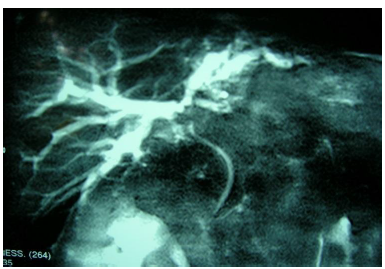

Paciente de 62 anos deu entrada no pronto socorro com quadro de icterícia, perda de peso (mais de 20 Kg nos últimos 4 meses) e desconforto abdominal. No exame clínico, apresentava dor à palpação do hipocôndrio direito. Estava afebril no momento. Durante a propedêutica inicial, evidenciou-se bilirrubina total de 23,5 mg/dl com predomínio da fração direta, enzimas canaliculares muito elevadas, aminotransferases discretamente elevadas, hemograma normal. Solicitada ressonância magnética de abdômen com colangiorressonância para estudo do caso.

|

São critérios de irressecabilidade nesses tipos de lesões, EXCETO:

Analise as afirmativas a seguir e assinale a alternativa INCORRETA.